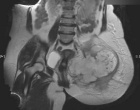

53 year old female with pelvic pain and fevers

History of left hip disarticulation due to a 2005 motor vehicle accident